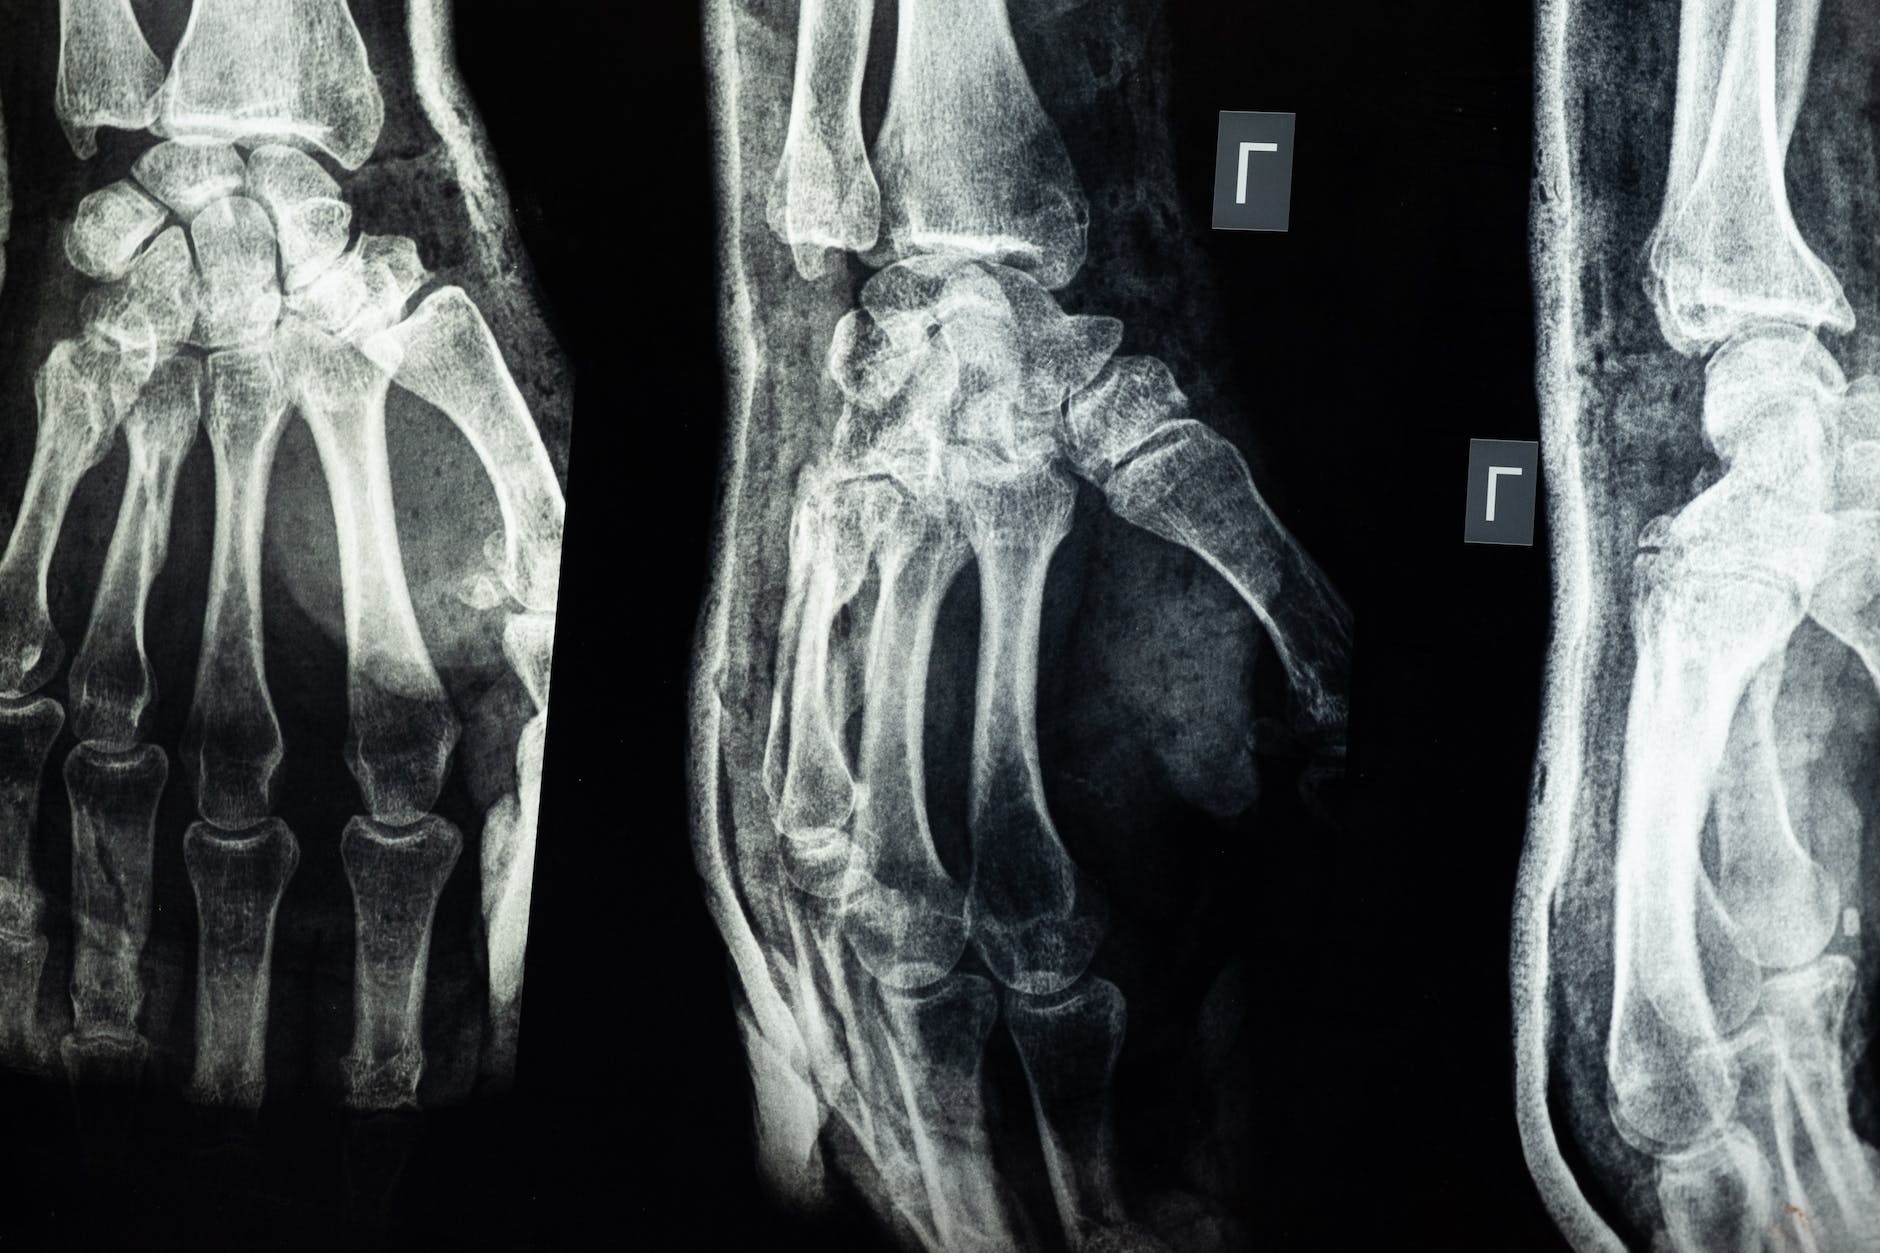

Contrary to popular belief, our bones are not static. They are not “frozen in form” like a plastic Halloween skeleton. They are dynamic, growing, shifting, and forming.

When we break a bone, bone cells grow back slowly and the fracture or break heals. Your bones are alive! And like the rest of your body, your bones want to heal – and they do, when we know how to properly care for them, and feed them.

Yes, calcium is one of the major mineral components of bone, and deficiency can lead to osteopenia and osteoporosis. If you are looking to heal bone damage from arthritis, calcium is an important piece of the puzzle – along with everything else discussed here. But we want APPROPRIATE levels in the right balances. Most of this can come through food. Supplement mindfully if needed.